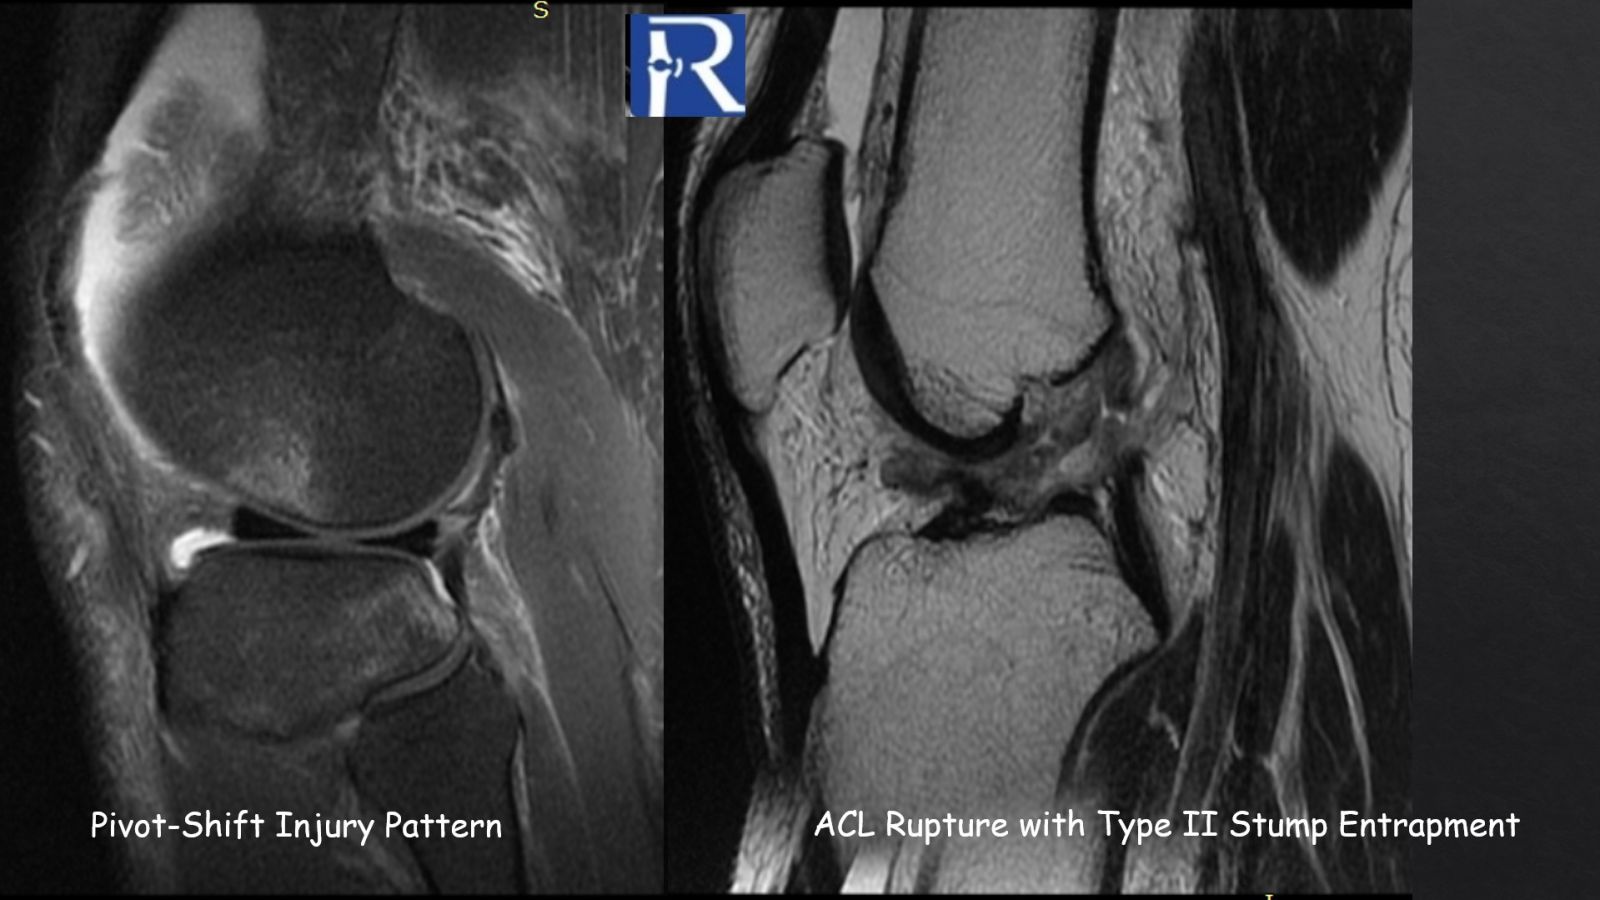

In more severe translational injuries, the torn ACL remnant may flip anteriorly and become entrapped within the intercondylar notch.

Type II stump entrapment represents the acute morphology:

- Anterior displacement of residual fibers

- No discrete nodular mass

- Possible mechanical extension block

If unrecognized, repetitive impingement may result in fibrotic remodeling, progressing into a Type I configuration resembling a cyclops lesion.

Thus, Type II stump entrapment may represent the precursor stage of anterior arthrofibrosis.